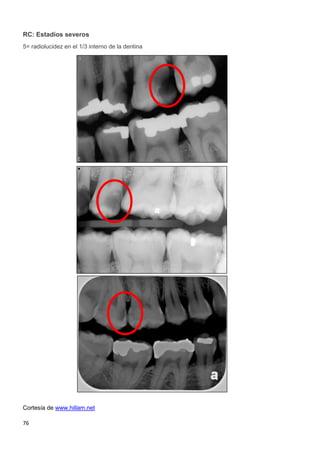

recomendado para niños ≤ 6 años. (SIGN 1---)

67,76

MNO: Sellantes a base

de resina/ionómero de

vidrio (SIGN 1+ / 1---)

65,79

MNO: Sellantes a base de

resina /infiltrantes

(SIGN 2--) 87

MNO: Higiene oral con crema dental fluorada (1000 ppm) cuando